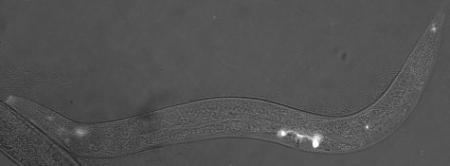

Glowing sensory cells in the worm that make complement factor H protein. Credit: PNAS

Vogel’s team found a worm version of complement factor H protein located in the sensory neurons that help the worms detect chemicals, food, touch, and temperature. The protein appeared specifically in the middle region of the sensory neuron’s little antennas, known as cilia (that do the work of sensing the environment), just next to another known important antenna protein called inversin. However, in worms bred to lack complement factor H, they found the inversin spread throughout the antennas rather than remaining in the middle of the antennas.